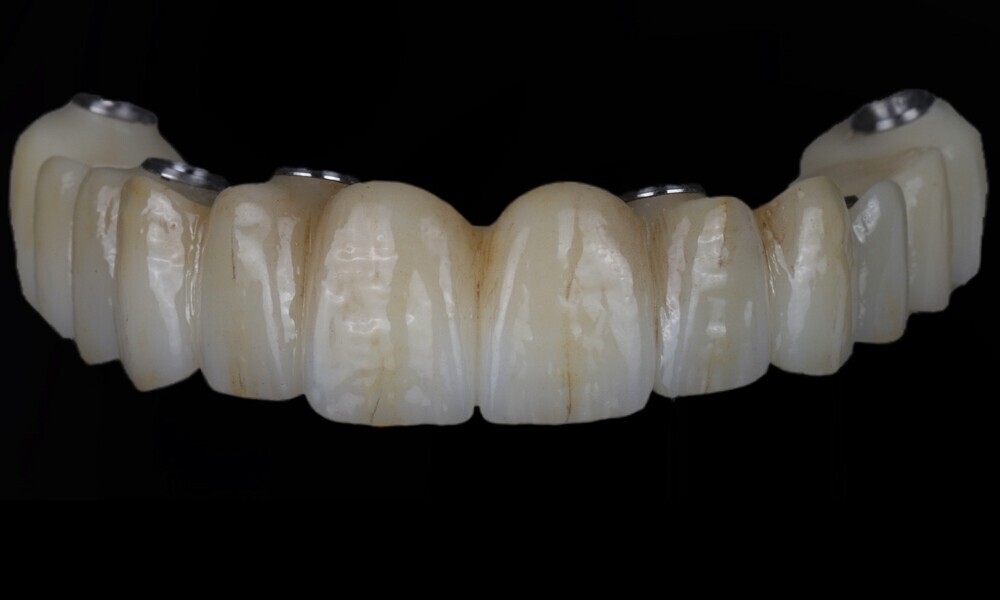

During the next visit, the milled prototype and verification jig were tried in, and the design and manufacturing of the final prosthesis were completed (Figs. 47 & 48). The final abutment utilised was Variobase for bridge (Straumann), placed on top of the screw-retained abutments. The material chosen for the final prosthesis was monolithic zirconia (Figs. 49 & 50).